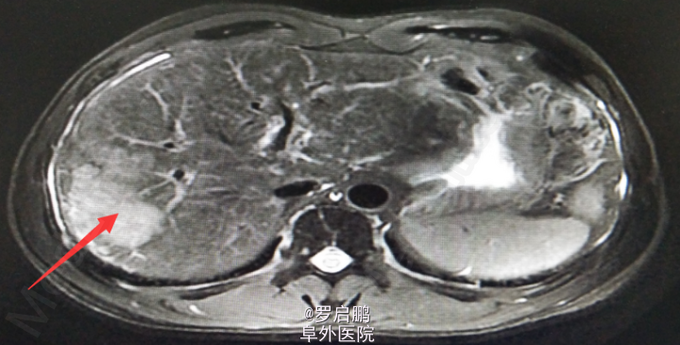

患者 男 48岁 主诉:发现肝脏占位半月 现病史:半月前患者因慢性乙型肝炎复查腹部超声发现右肝占位 既往:慢性乙肝20年,未规律治疗。 个人史:吸烟史25年20支/天,饮酒史13年,白酒2两/次。

超声:右肝高回声光团,胆囊、肝内外胆管、脾脏、双肾未见异常 腹部MRI:肝右叶占位 腹部平扫+增强:肝右叶占位,肝内多发小密度,左肾囊肿,腹膜后淋巴结肿大

肝右叶占位,肝癌? 前入路右半肝切除,LC 鉴别诊断:原发性肝癌;肝转移癌;肝海绵状血管瘤;肝腺瘤;血管平滑肌脂肪瘤。

注意术中循环维持,备血、血浆。术中平稳。术中病理:(右半肝)低分化胆管腺癌,可见坏死,肝内可见多发卫星灶,紧邻肝被膜,切缘未见特殊。术后恢复良好出院。